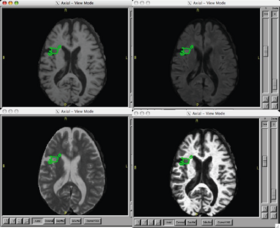

| − | |[[Image: | + | |[[Image:Lupus.png|thumb|280px|Caption 2]] |

- The pipeline attempts to solve the problem of segmenting white matter lusions in lupus. The capability is aimed at clinical researchers.

- The state of the art is a work in progress in N-SLE. There are many approaches that attempt to solve lesion classification in Multiple Sclerosis. Some of these approaches are automated or semi-automated; however, all automatic approaches suffer a lack of a gold standard. It is difficult for humans manual raters to agree on fuzzy boundaries across different image constrasts (e.g., T1, T2, FLAIR).